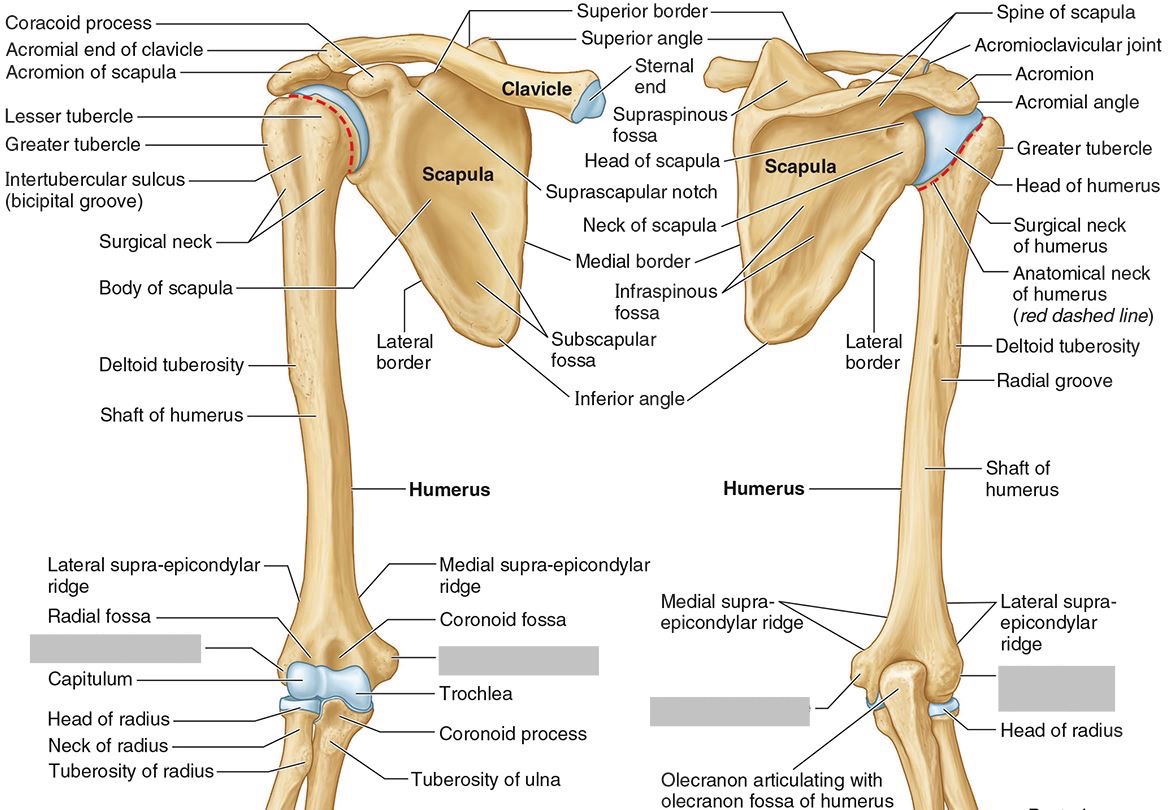

What part of the humerus is this?

The head of the humerus articulates with the scapula at the glenohumeral joint.

What part of the humerus is this?

The anatomic neck is an indentation distal to the head and provides an attachment for the fibrous joint capsule of the glenohumeral joint.

What part of the humerus is this?

The greater tubercle lies lateral and distal to the anatomic neck.

What part of the humerus is this?

The lesser tubercle lies on the anterior/medial side of the humerus, just distal the anatomic neck.

What part of the humerus is this?

The intertubercular (bicipital) groove lies between the greater and lesser tubercles.

What part of the humerus is this?

The surgical neck is a narrow area distal to the tubercles. It is a common site for proximal humerus fractures.

What part of the humerus is this?

The humeral shaft features the deltoid tuberosity laterally for the distal insertion of the deltoid muscle.

What part of the humerus is this?

The radial groove is an oblique depression that contains the radial nerve and deep brachial artery.

Which parts of the humerus is this?

The medial and lateral epicondyles are distal prominences to which many forearm tendons attach, near the elbow joint.

Which parts of the humerus is this?

The medial and lateral supracondylar ridges extend superiorly from the medial and lateral epicondyles.

Which parts of the humerus is this?

The trochlea and the capitulum (the condyles) are the most distal surfaces of the humerus, where it articulates with the forearm bones at the elbow joint

What part of the humerus is this?

The olecranon fossa is a posterior depression above the trochlea that receives that olecranon process of the ulna

What part of the humerus is this?

The coronoid fossa is an anterior depression above the trochlea that receives that coronoid process of the ulna.